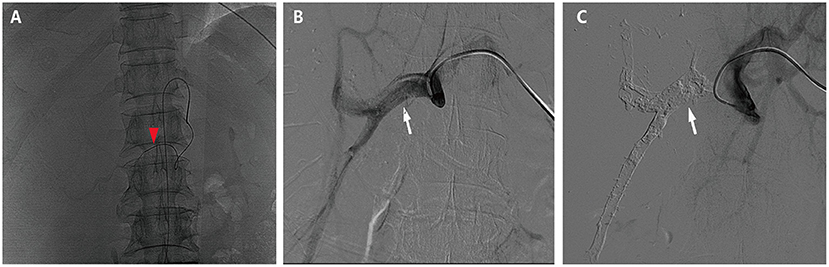

HAIC with the mFOLFOX regimen (oxaliplatin, 85 mg/m2 intra-arterial infusion; leucovorin, 400 mg/m2 intra-arterial infusion; and fluorouracil, 400 mg/m2 bolus infusion and 2,400 mg/m2 continuous infusion) was performed initially. The infusion microcatheter was selectively placed into the common hepatic artery, which was the main feeding artery to the tumor (Figure 2A). After 3 days of HAIC, biological glue was utilized to embolize the right branch of the portal vein (Figures 2B,C), resulting in a brief increase in alanine transaminase (ALT) to 338.6 U/L, aspartate aminotransferase (AST) to 632. U/L, and total bilirubin (TBIL) to 32.4 umol/L. Liver function normalized with medication within 3 days, and Lenvatinib (8 mg per day) plus Sintilimab (200 mg per 3 weeks) were administered subsequently, causing no significant adverse events. After 5 weeks of multimodality therapy, follow-up CT scans showed remarkable regression of the tumor with complete disappearance of intratumoral enhancement on the artery phase (Figure 3A) and increased distance between the tumor and the middle hepatic vein (Figure 3B). The FLR/SLV reached 67.74% (Figure 3C), and the Child-Pugh score was 5, which met the requirements of the surgery. One week later, laparoscopic right hemi-hepatectomy was successfully performed with a >1-cm surgical margin. The gross of the resected specimen showed obvious hemorrhage and necrosis of the tumor (Figures 4A,B). Postoperative pathology revealed an encapsulated tumor with massive hyalinization, necrosis, lymphocyte, and granulocyte infiltration, and no viable tumor cells (Figure 4C). The patient was discharged at the 7th day after the operation without any complications. He was advised to stop drinking and follow up regularly. At the 3-month follow-up, no significant evidence of recurrence on imaging or laboratory tests was observed. The timeline of clinical events is shown in Figure 5.

Figure 2. Hepatic artery infusion chemotherapy and portal vein embolization. (A) The tumor was mainly fed by both right and left hepatic arteries, so the infusion microcatheter was selectively placed into the common hepatic artery (the red arrow head). (B) The right branch of the portal vein before embolization (the white arrow). (C) The right branch of the portal vein after embolization (the white arrow).